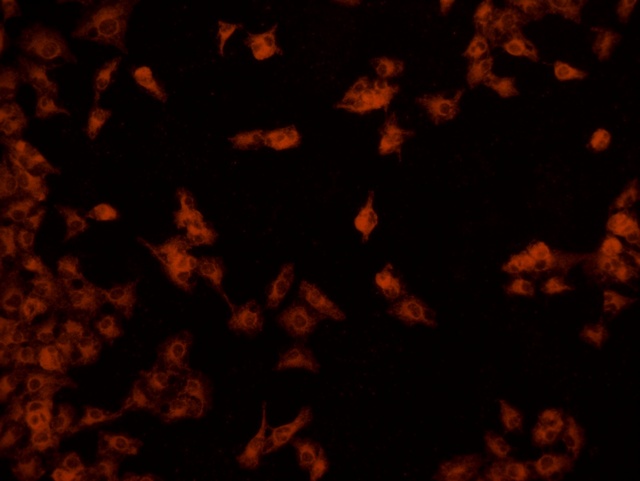

南華大學在生物醫學研究領域一直走在學術前沿,近日,該校引進Mshot明美的倒置熒光顯微鏡MF52-N,搭配顯微鏡相機MSX2,為細胞切片標本的研究提供了強大的技術支持,進一步提升了科研實力。

MF52-N倒置熒光顯微鏡以其數顯LED熒光模塊和深度優化的光路設計,成為細胞切片觀察的理想選擇。其簡單易用的熒光激發操作,大大降低了實驗難度,提升了工作效率。同時,該顯微鏡還能提供高質量的相襯、熒光和明場成像,確保科研人員能夠捕捉到細胞切片的每一個細節。

在南華大學的實驗室中,科研人員正借助這套先進的顯微系統,對細胞切片標本進行深入探索。

此外,MSX2顯微鏡相機的加入,更是如虎添翼。這款相機以其高分辨率和敏銳的圖像捕捉能力,記錄了實驗過程中的每一個重要瞬間,為數據分析與論文發表提供了有力支持。